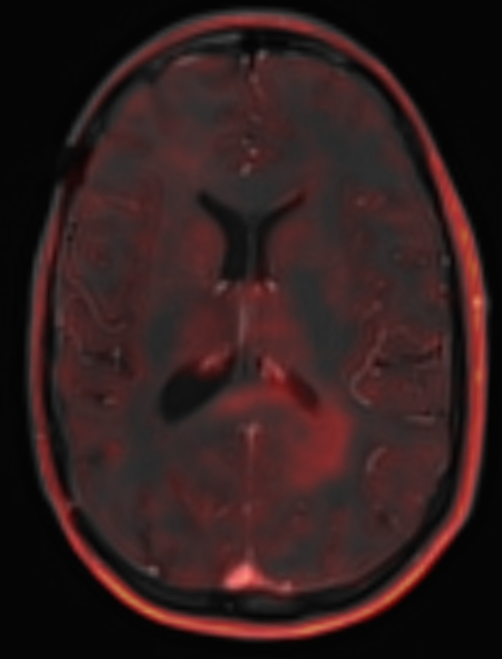

One month later (patient did not undergo tratment yet), MRI finding becomes clearer

1748327624012.png